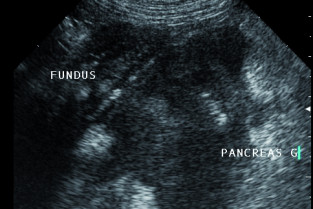

- Intégrer les examens complémentaires dans la démarche diagnostique (test enzymatiques, imagerie,...).